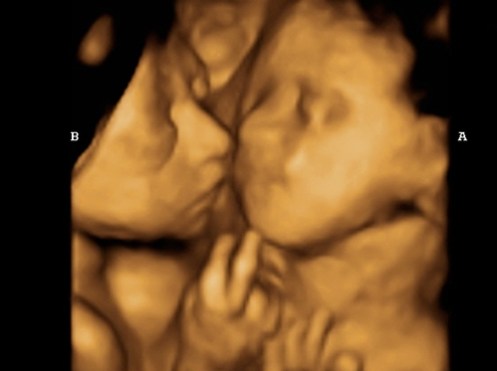

أرواح لم يسمع لها صوت ..

استقبلتها الحياة ..

بالموت !!

أيدي لم تدنس ..

و عيون لم ترى !

وجه لم يصافحنا ..

و يد .. لم تلعب !!

الوسوم: لندن, هروب, ٢٠١٦, اغسطس, توأم